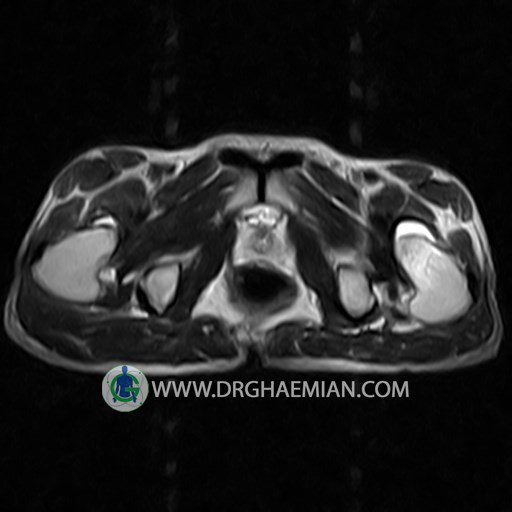

HIP JOINT MRI

( without contrast )

Technique : coronal STIR , coronal T2 , Axial T1 , axial T2 .

REPORT:

The femoral heads and acetabula are normal shape , signal intensity and the femoral heads are well covered by the acetabular margins .

The joint spaces are of normal width without fluid collection .

The articular surfaces are smooth and congruent and show normal cortical thickness .

Each femoral shaft has normal margins and contains a normal bone marrow signal .

The imaged muscles and the lesser pelvis show no abnormalities .

– Heterogeneous signal change (high T2/STIR , low T1) in proximal metaepiphysis of left femur without articular surface irregularity suggestive for bone bruise (stress fracture?), osteomyelitis & arthritis and marrow infiltration (less probable)

– Left hip joint effusion suggestive for synovitis

are seen.

COMMENT: Clinical correlation and MRI with contrast are recommended.